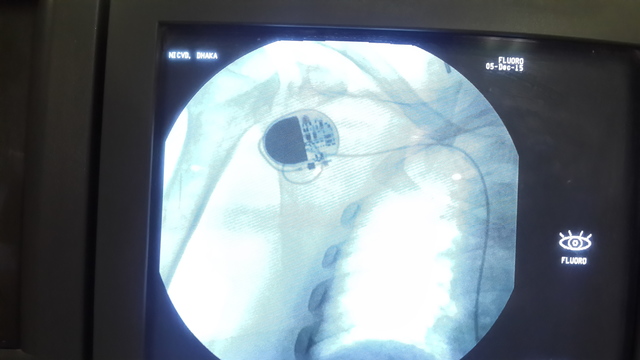

• Implantable Pacemakers

Implantable Pacemakers

Medtronic, Dr. William Chardack and Engineer Wilson Greatbach developed the first commercially produced implantable pacemakers for heart patients. The surgeons were able to implant this device into patient’s heart in order to regulate proper heart rate and rhythm.

• Development in Pacemaker

Development in Pacemaker

Medtronic improved the functions of the pacemaker. It introduced rate-responsive within pacemakers which basically adjusts an appropriate pacing rate to counterpart patient’s level of physical activity instead of a fixed pacing rate.

• Smallest Pacemaker

Smallest Pacemaker

Medtronic introduces the smallest and efficient pacemaker. This pacemaker only weighted 17grams, with dimensions of 40mm by 32mm by 7mm thickness. This pacemaker was targeted for both adults and children.

• Pacemaker for MRI Diagnosis

Pacemaker for MRI Diagnosis

Medtronic developed a pacemaker specifically made MRI (magnetic resonance imaging) surroundings or environments. Pacemakers had certain limitations, but with this advancement, patients now have access to latest diagnostic technologies.